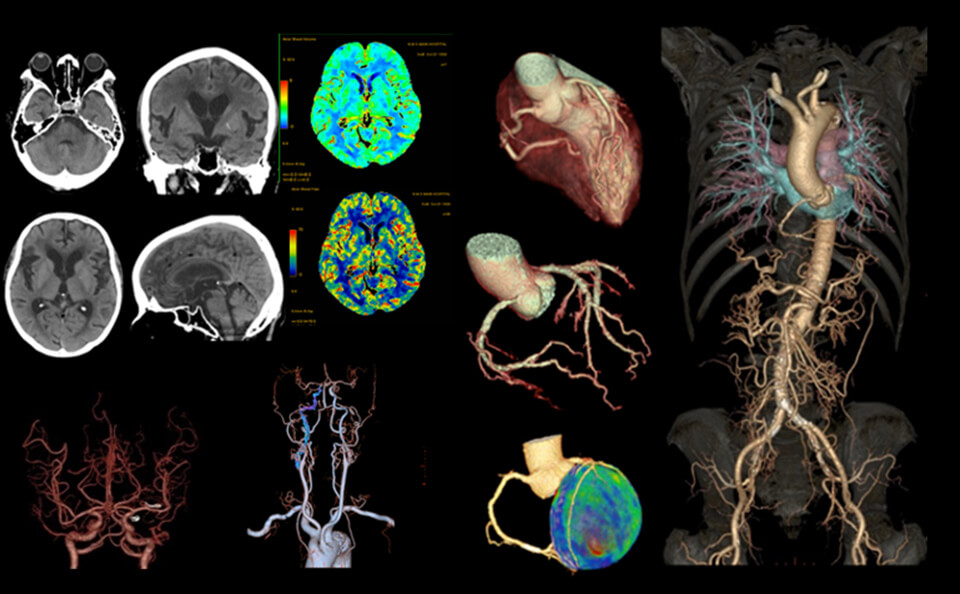

上記のCT装置より得られた⾝体の断⾯画像を⽤いて3次元、4次元画像を作成することができます。例えば以下の画像のように⼼臓や脳、全⾝の⾎管を⽴体的に観察することで、⾎管⾛⾏の把握、⽯灰化や狭窄部位の発⾒に役⽴てることができます。